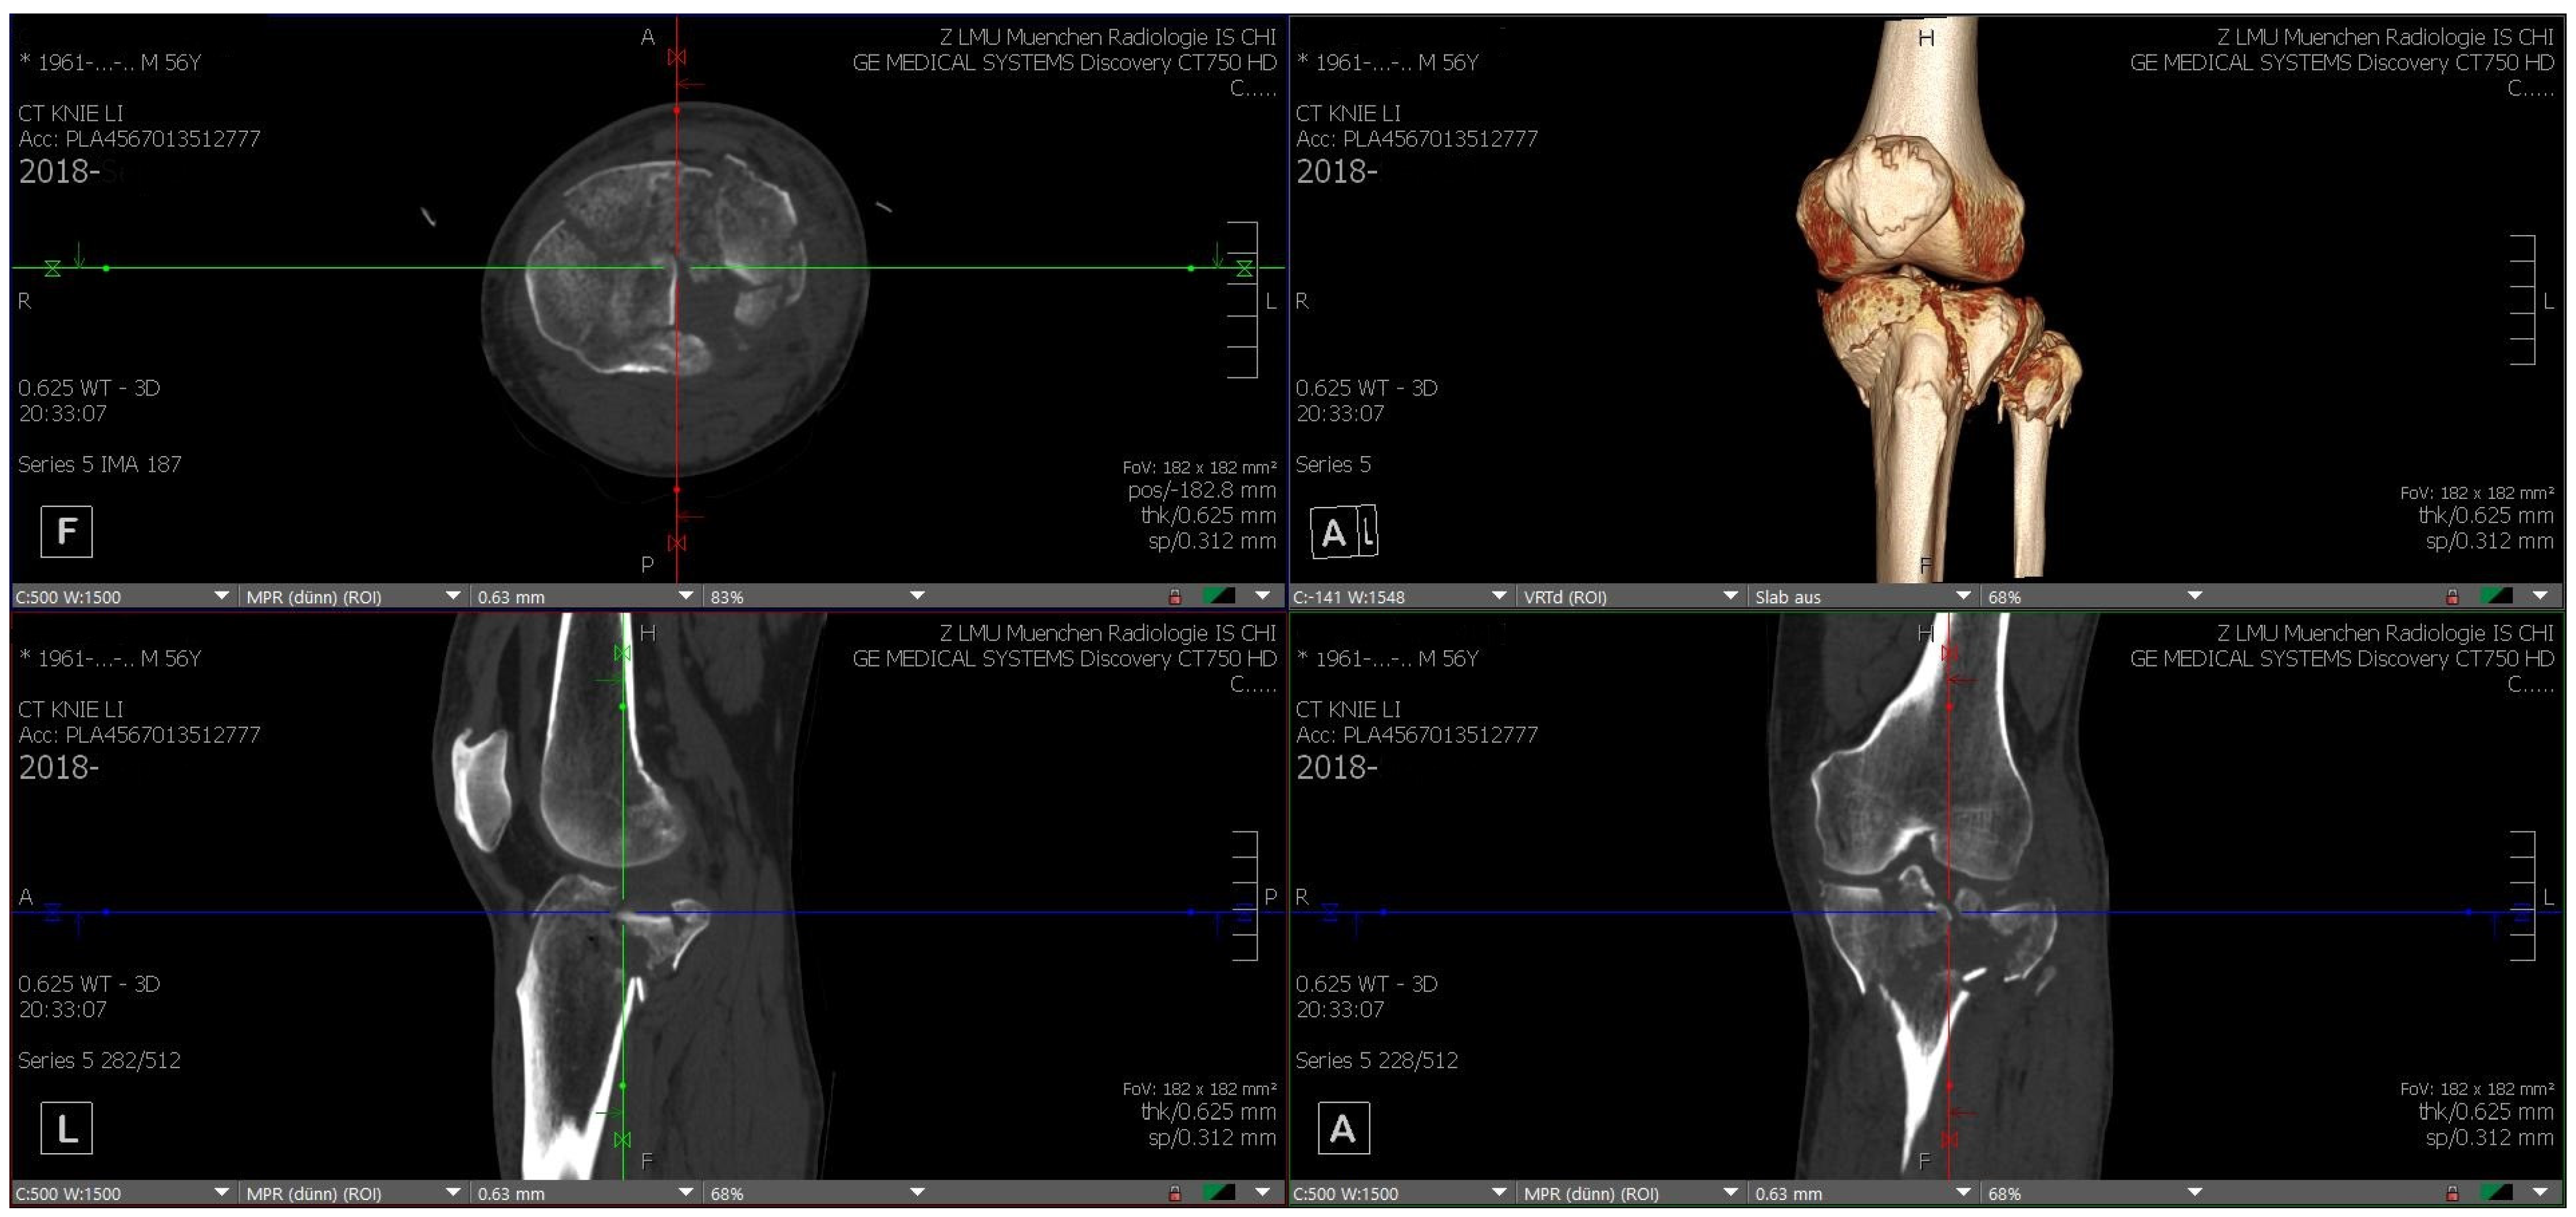

Each TPF was presented in three steps to the participating surgical specialists in trauma surgery. First by CT, including 3D CT reconstruction (software: Visage 7.1.16—Visage Imaging, San Diego, CA, USA; Figure 1), subsequently on MR glasses (Figure 2), and finally as a 3D-printed model (Figure 3).

Figure 1.

CT (axial, sagittal, coronary) including 3D reconstruction of fracture 1 (source: Visage 7.1.16—Visage Imaging, self-modified).